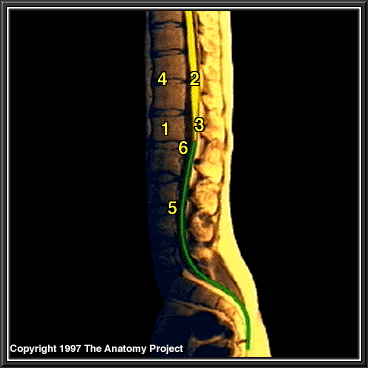

Lower Third of Spinal Cord, MRI

Vertebral body

Spinal cord

Conus medullaris

Intervertebral disc

Filum terminale (internum)

Subarachnoid space